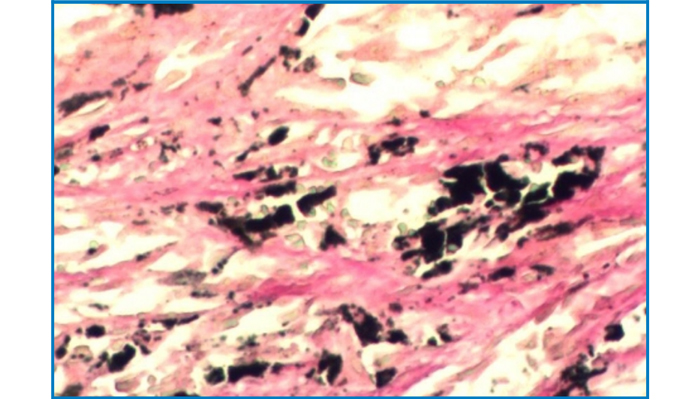

Melanin Stain (Ferrous sulfate staining method)

Melanin Stain

(Ferrous sulfate staining method)

Intended for staining examination of histological melanin.